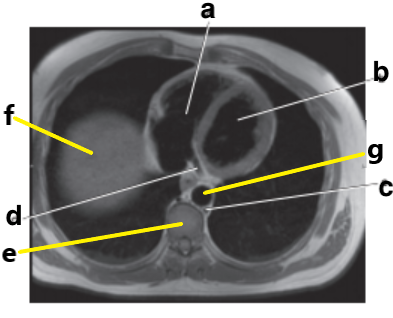

What is letter b ?

Left ventricle

What is letter a ?

Right ventricle

What is letter d ?

What is letter c ?

Hemiazygos vein

What is letter g ?

Right atrium

Left atrium

Pulmonary trunk

Bicuspid valve / LT AV valve

Descending thoracic aorta

Which letter is the Pulmonary trunk ?

d